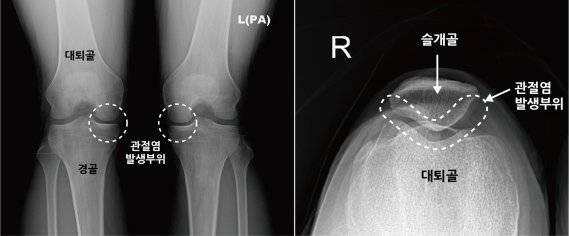

우리가 일반적으로 알고 있는 무릎 관절염(퇴행성 관절염)은 대퇴골과 경골 사이에 있는 연골 손상으로 관절염이 진행될수록 무릎의 관절 간격이 좁아지기 때문에 심한 경우, X-ray만으로도 비교적 쉽게 진단이 가능하지만 슬개대퇴관절염의 경우 질환이 어느 정도 진행된 경우에도 X-ray 검사상 이상 소견을 발견하기 어렵기 때문에 진단이 쉽지 않다.

슬개대퇴관절염은 슬개골(무릎 앞에 있는 삼각형의 뼈)과 대퇴골 사이 연골에 손상이 발생하거나 선천적으로 슬개골이 대퇴골에 제대로 맞자 않아 무릎이 움직일 때 슬개골이 어긋나면서 연골에 스트레스가 가해져 발생한다.